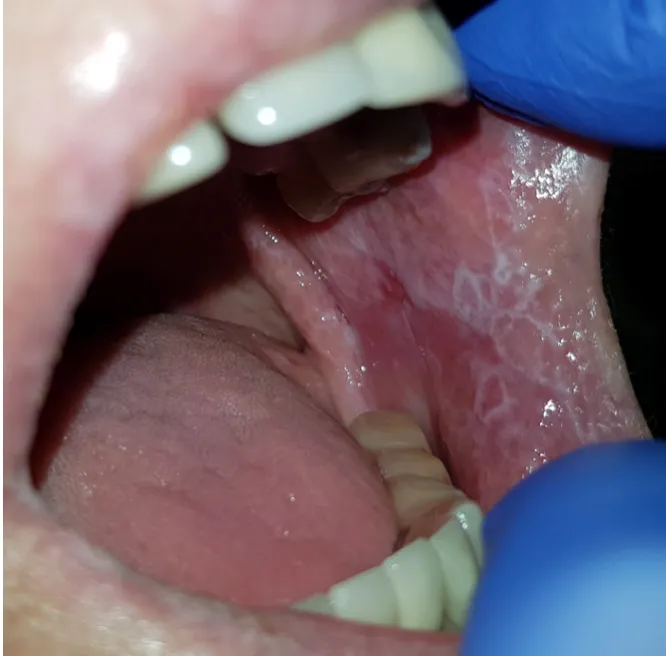

Liszaj płaski jamy ustnej potrafi przybierać różne formy, co często utrudnia jego wstępne rozpoznanie. Najczęściej spotykaną postacią jest tak zwana postać siateczkowata. Charakteryzuje się ona obecnością białych, koronkowych linii, grudek lub plamek, które układają się w charakterystyczną siateczkę Wickhama. Zmiany te są zazwyczaj bezbolesne i mogą być wykryte przypadkowo podczas rutynowej kontroli stomatologicznej.

Znacznie bardziej uciążliwa dla pacjentów jest postać zanikowa lub nadżerkowa. W tym przypadku błona śluzowa staje się czerwona, cienka i podatna na uszkodzenia, tworząc bolesne nadżerki, a nawet owrzodzenia, które mogą krwawić. To właśnie ta postać powoduje największy dyskomfort, utrudniając jedzenie, mówienie, a nawet połykanie.

Gdzie najczęściej pojawiają się zmiany? Typowe lokalizacje

Zmiany w przebiegu liszaja płaskiego mogą pojawić się w różnych miejscach jamy ustnej, ale istnieją pewne typowe lokalizacje. Najczęściej obserwujemy je na wewnętrznej stronie policzków, tworząc wspomnianą już siateczkę Wickhama. Inne miejsca to język (zwłaszcza jego boczne powierzchnie), dziąsła, a rzadziej podniebienie czy wargi. Czasem zmiany mogą występować jednocześnie w kilku obszarach.